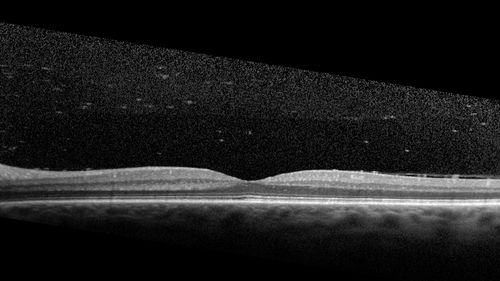

56 year old man who became very sick after eating venison at the end of December 2019.  Presented 6 weeks later with a scotoma.  Initial photos show presentation with 20/63 vision.  Vision dropped to 5/200.  All tests (including PCR of anterior chamber tap) were negative except serum toxoplasmosis IgG and IgM.  Vision improved to 20/32 but the scotoma remained on oral trimetheprim/sulfa

Acquired Toxoplasmosis Retinitis Para Foveal - Following Venison Consumption